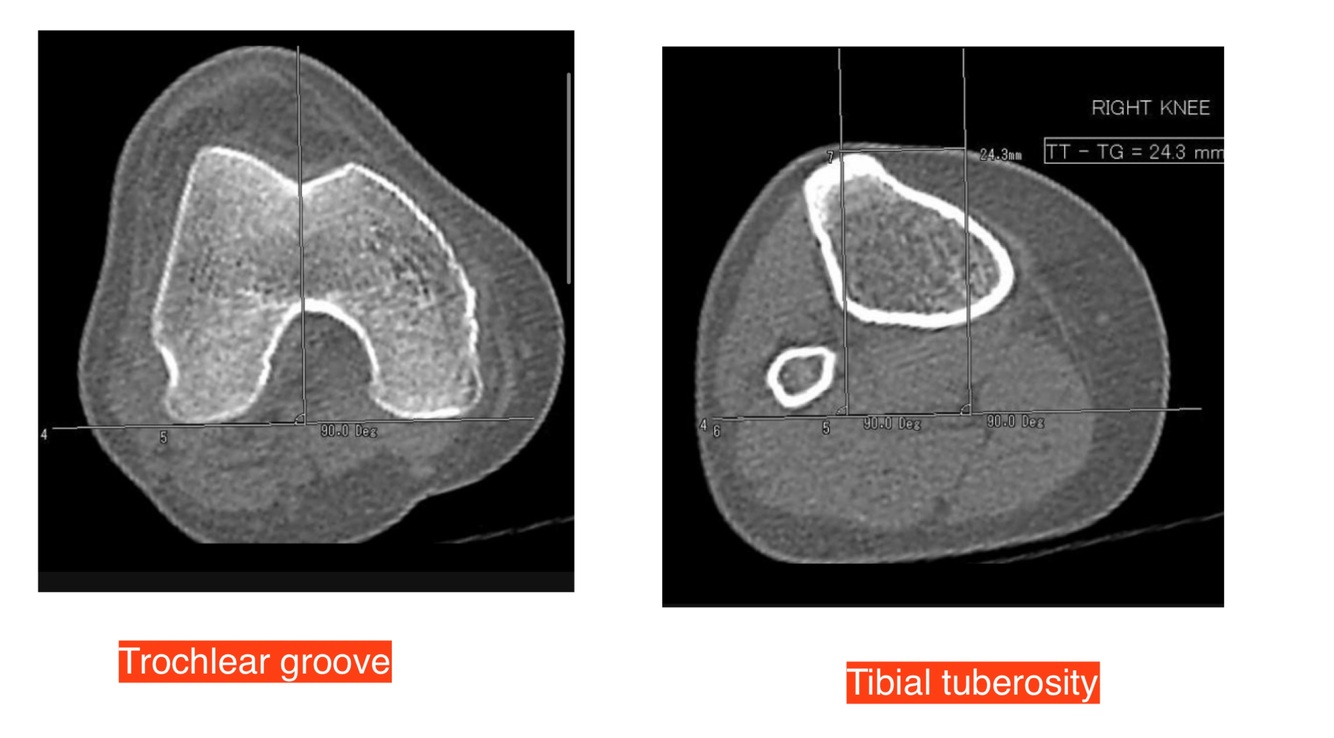

@# 22. Which statement is not associated with transient patellar dislocation?

1. B. A tibial tuberosity to trochlear groove distance of <1.5 cm.

Transient patellar dislocation is the dislocation of the patella laterally and subsequent relocation.

Trochlear dysplasia, patella alta (increase in the ratio of the patella tendon to the patella length) and an increase in the tibial tuberosity trochlear groove (TT-TG) distance are associated factors.

TT-TG >20 mm is abnormal and 15-20 mm is considered borderline change.

TT-TG less than 15 mm is within normal limits.

Contusional marrow oedema is often seen in the medial patellar facet and the lateral femoral condyle.

The medial patellar retinaculum and/or medial patellofemoral ligament (MPFL) may be torn or show a pattern of strain injury.